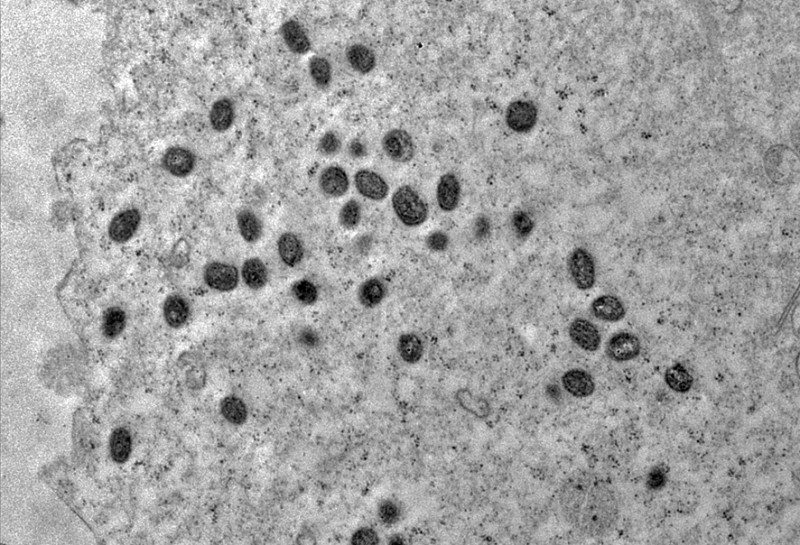

© Débora F. Barreto-Vieira/IOC/Fiocruz

Saúde Há 3 anos

Mpox ainda é problema de saúde pública, dizem especialistas da Fiocruz

Foram confirmados 22 casos em janeiro de 2023 no Brasil